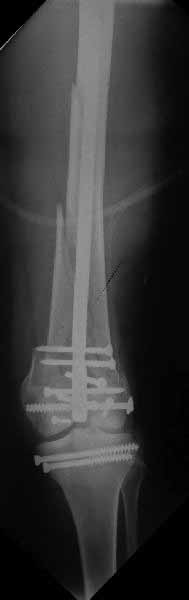

Ответ на эту часть Вашего поста – вложенный файл. Больная оперирована неделю назад по поводу открытого перелома дистального эпиметафиза бедренной кости. После операции она идёт в рентгенкабинет для выполнения послеоперационной контрольной рентгенографии, представленной на слайдах 10 и 11. Узнав, почему её фотографируют, просила передать Вам, Антон, привет.

-искренне рад (я еще не потeрял такую способность))) за удачно прооперированную Вами пациентку, хотелось бы отследить ее случай и далее.